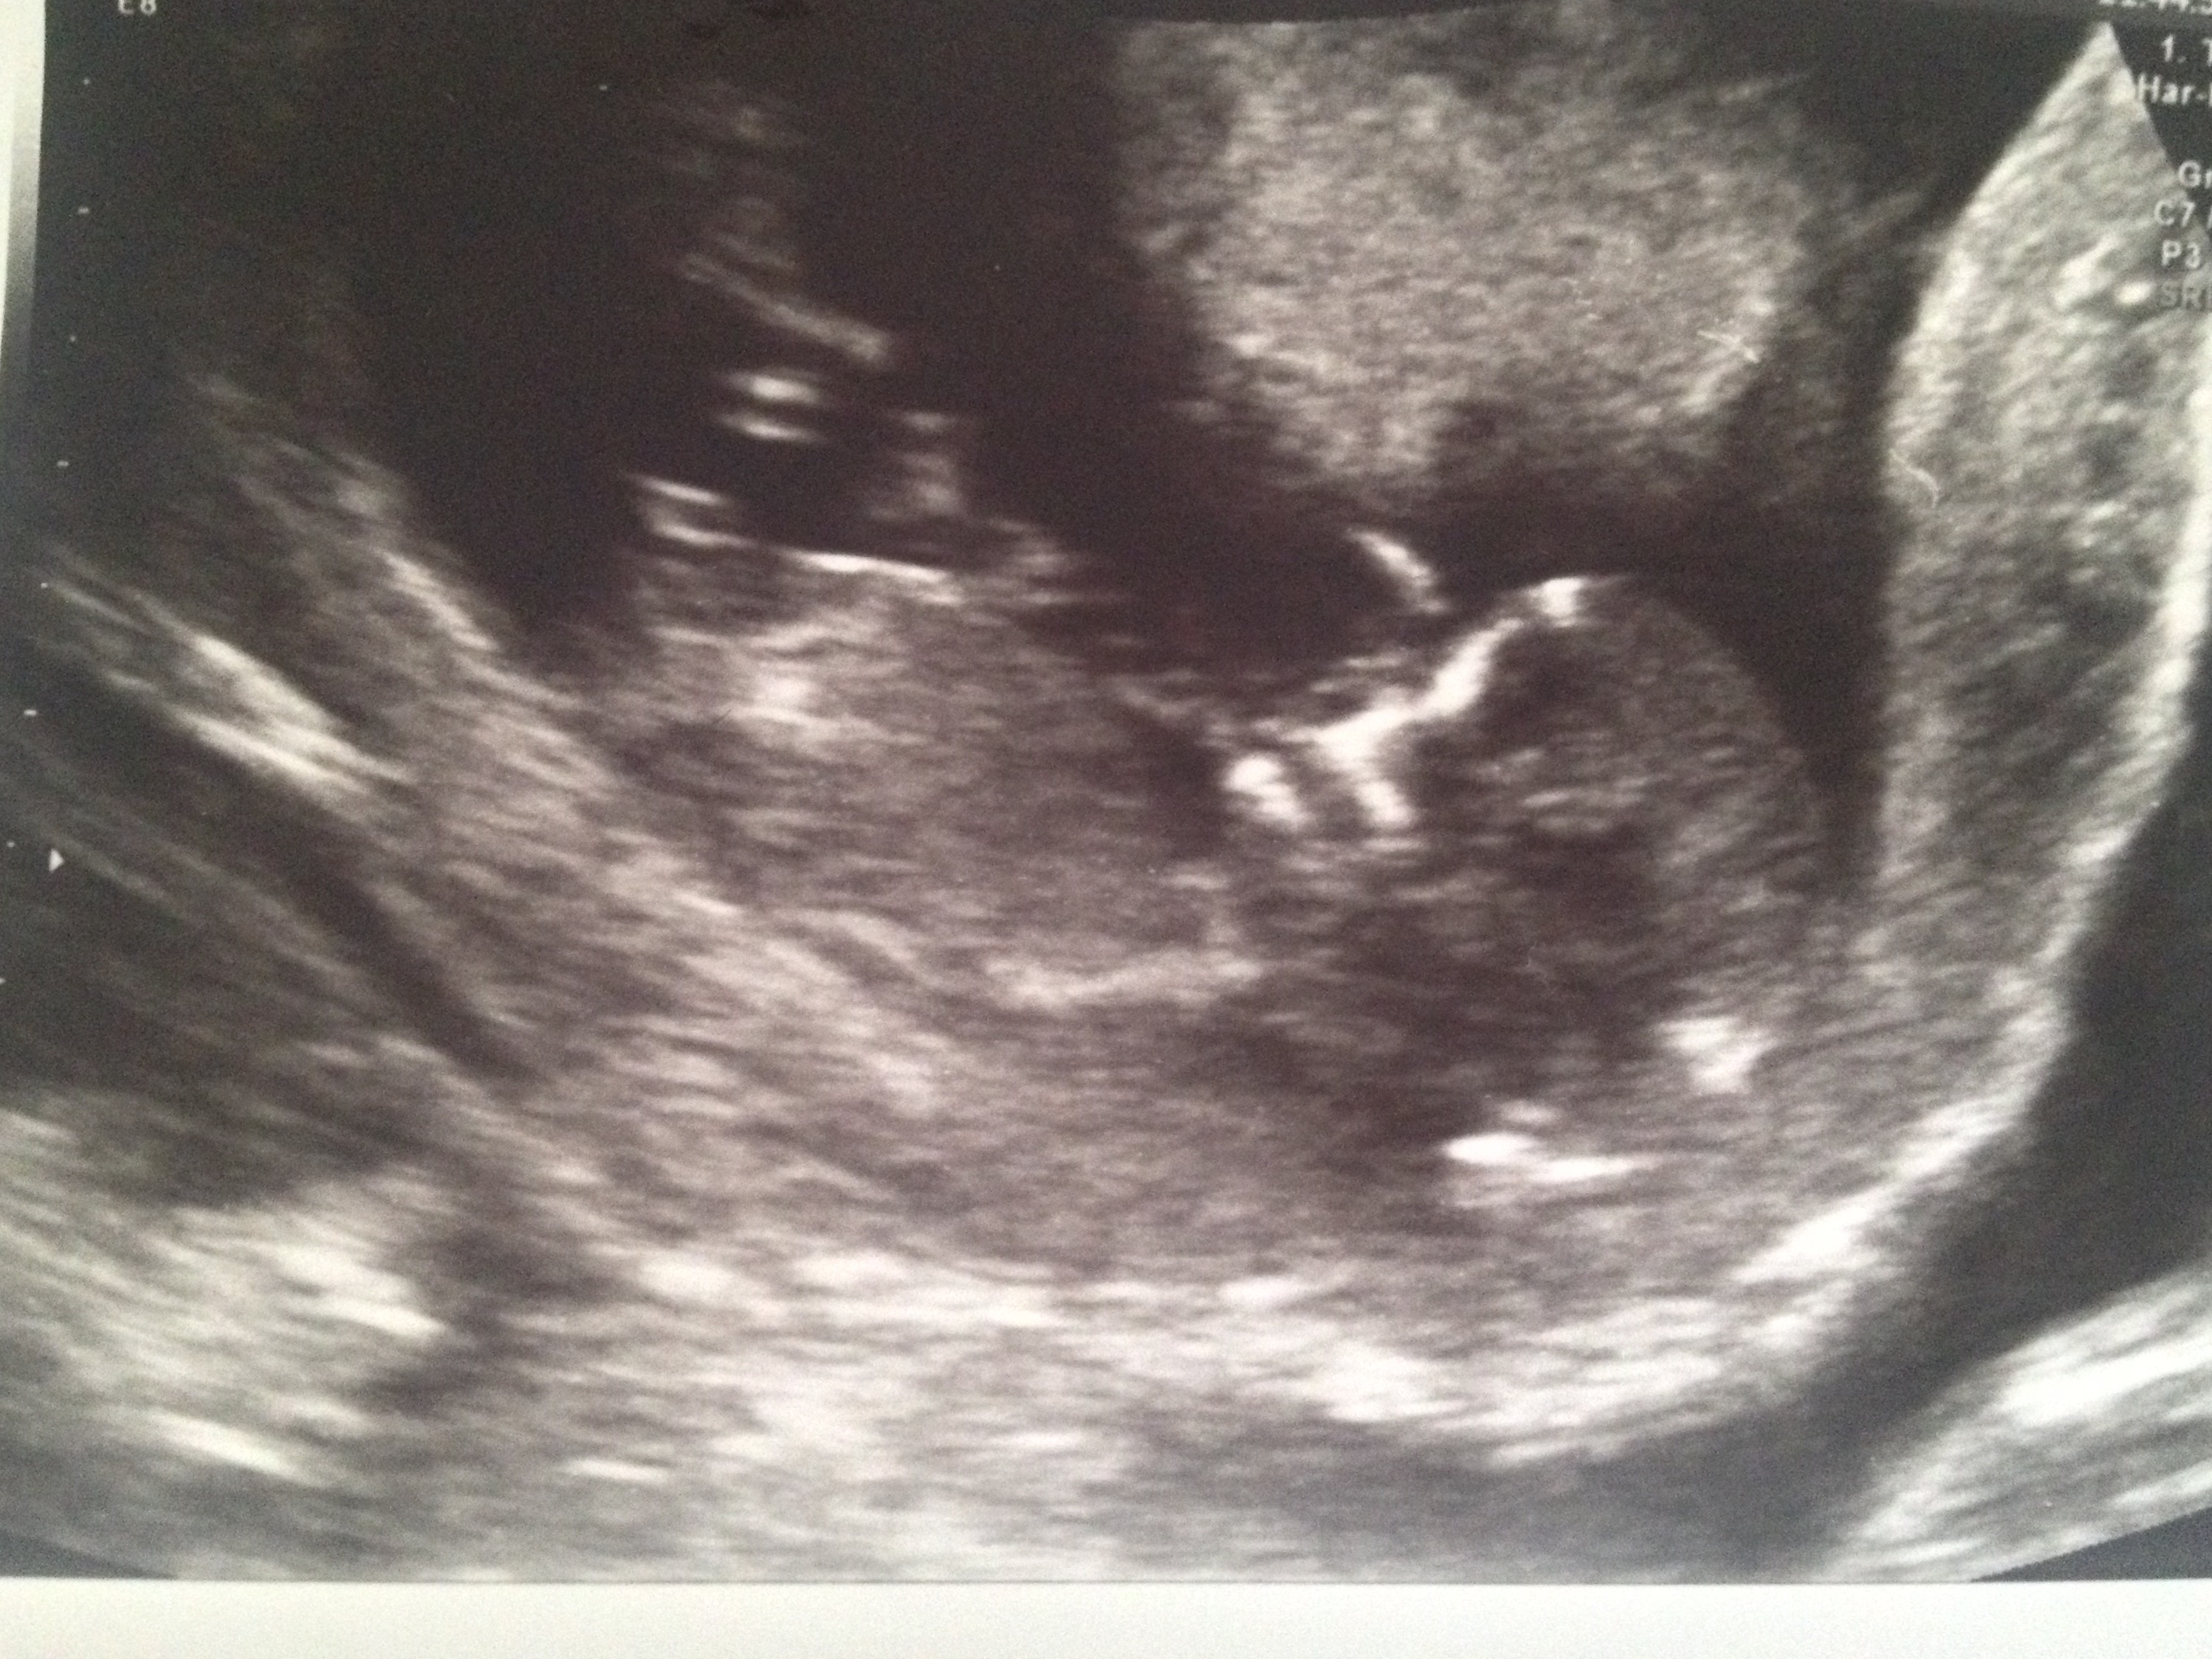

Any guesses? X